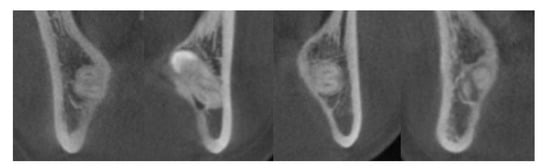

2.3. Surgical Procedure and Identification of IAN Exposure

3.2. Radiographic Characteristics in the Exposed Group